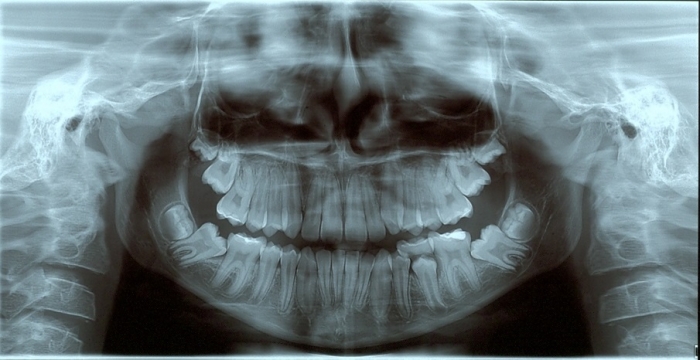

Rx Panorâmico Inicial - Clínica Cliniface

Rx Panorâmico Inicial